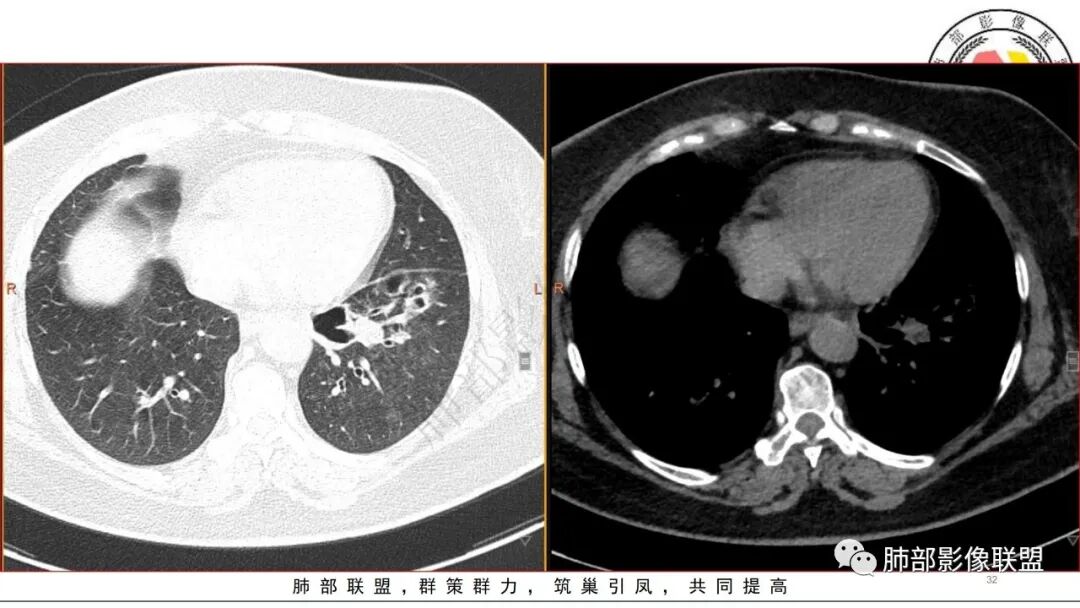

5.扫描范围内未见肝脏密度异常影。

4.肺炎克雷伯杆菌肺炎病灶也易形成脓腔。本例患者未出现典型金葡感染影像学特征,患者临床表现相对“逍遥”缓慢,结合实验室检查,更符合肺炎克雷伯杆菌肺炎。

金葡应该也是血源性来源,因此也存在鉴别,区别在肝脏,肺克的血播是肝脏来源,金葡的血播可以各种来源,但是一般不会是肝脏来源,具体来说,金葡的SPE观察不那么典型,金葡可以形成更大的实变,肺克少一些,金葡的特征应该还是气囊,壁的张力更高,更薄,SPE似乎不明显,临床上皮肤软组织脓肿的有无,这个特征肺克应该不具有,但肺克一般有肝脓肿,没有的少见。